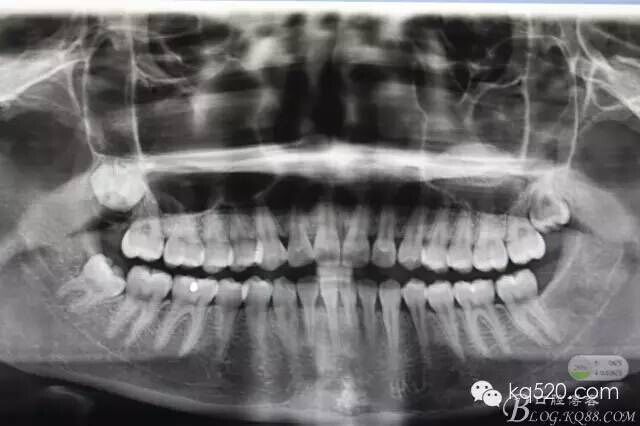

【臨床經驗】微小切口拔除埋伏智齒 --張東星

閆xx、女、19歲,主訴:右側下頜后牙不牙齦適數(shù)日。專科檢查:48未萌出、47遠中有深的盲袋、可探及牙冠。牙齦輕度紅腫,x光:48近中傾斜、雙根。診斷:近中埋伏阻生。建議拔除,患者同意治療方案,簽手術知情同意書。術前設計:考慮患者比較年輕,近中傾斜不大。計劃設計微切口、不分牙、微創(chuàng)拔除。

圖1.術前的x光影像檢查,48近中輕度傾斜。